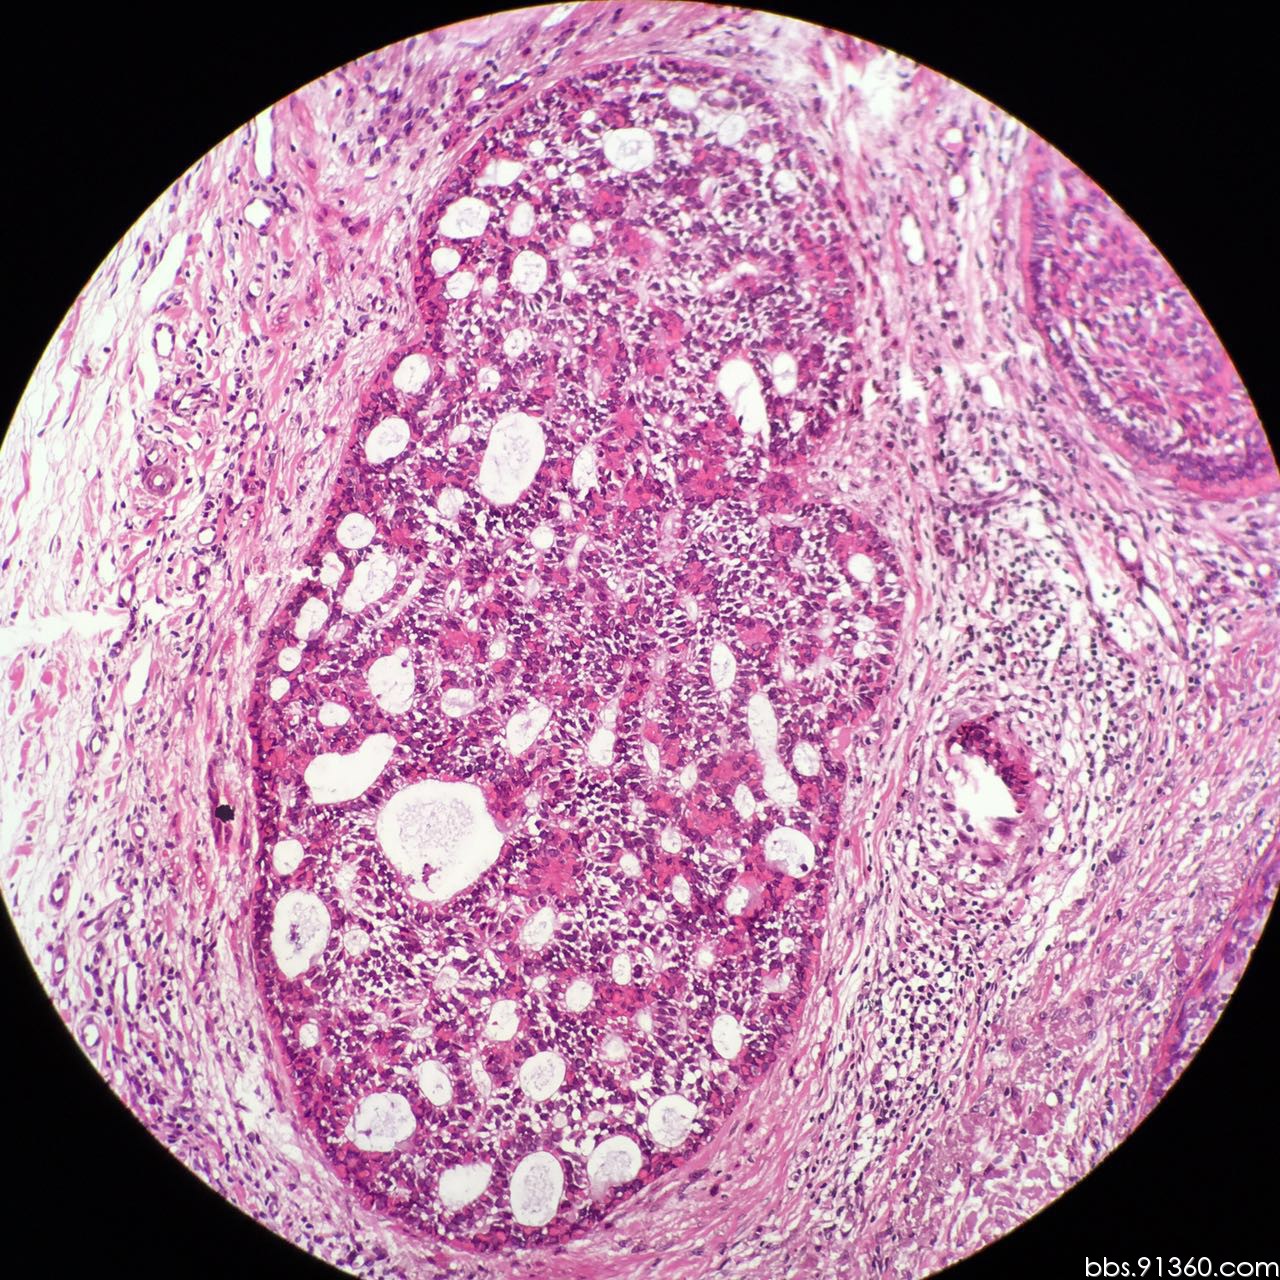

毛母细胞瘤恶变病例2016.05.04【91360皮肤沙龙案例37】

图片尺寸1280x1280

图片尺寸720x1280